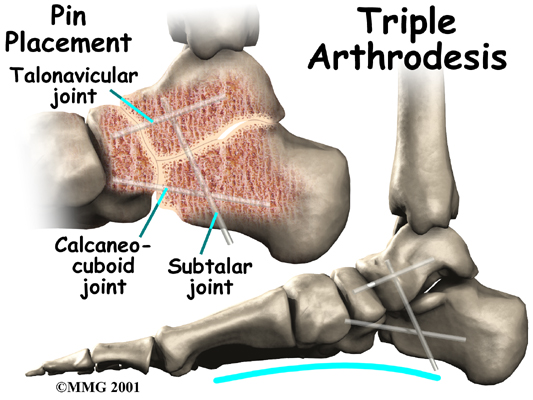

Fusion

Finally, in cases which have been neglected and a fixed flatfoot deformity is present, a fusion (or arthrodesis) of the foot may be required. A fusion is an operation where a joint between two bones is removed and the two bones on either side of the joint are allowed to grow together, or fuse. This type of operation is used to stop pain from joints that are worn out. It can be used to realign the bones when the mechanisms for maintaining normal alignment are lost, such as when the tendons and ligaments no longer work properly. Usually, several joints must be fused to control a flatfoot deformity that develops after a posterior tibial tendon rupture.

Significant improvement in your foot after surgery occurs gradually over a four-to-six month period of time. During that time, your physical therapist will progress your exercise program, but your appointments at Ari Levine PT, PC will decrease in frequency. For those patients who have had a fusion, there will be stiffness and loss of motion in the foot and/or ankle, so this should be expected. The amount and location of the stiffness depends on which bones were fused together.